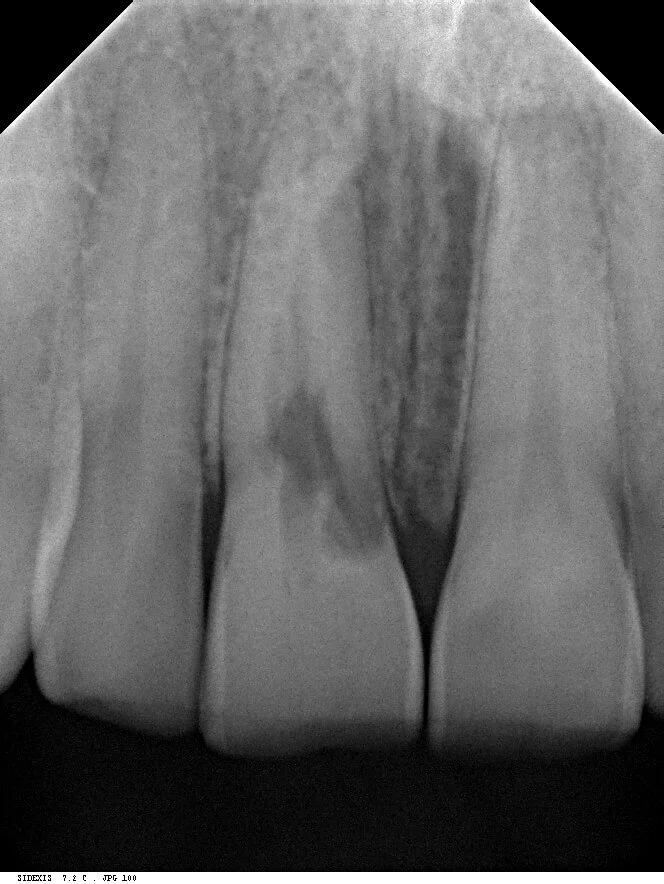

Pre-Treatment

The radiograph shows extensive internal root resorption making this tooth completely unrestorable. It also shows excellent bone height into proximally both at the mesial and the distal.